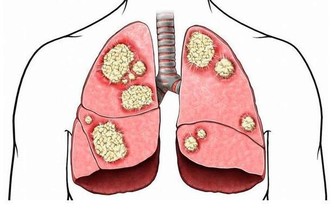

肺癌是中國發病率最高的癌症,也是死亡率最高的癌症。不管是何種癌症,我們都知道,一般發現時都是晚期,很難治愈。如果癌症早期能夠及時發現,經過治療後的五年生存率會大大提升。對於患者來說疾病的早發現要比“靈丹妙藥”見效好!

在德克薩斯州旅行結束後,Bill決定要仔細檢查一下自己的肺,畢竟他是一位有著55年菸齡的老煙民。在找到梅奧診所健康系統肺科的Adel Zurob醫生,醫生了解情況後建議Bill做一項肺癌篩查(低劑量CT)。檢查結果顯示:右肺有一個小的癌變結節。通過進一步的正電子發射斷層掃描(PEC-CT),顯示肺部以外沒有擴散或轉移的徵象。醫生建議,立即進行手術治療。

在醫生切除了Bill的癌變病灶後,還為他進行了胸部檢查以確定是否有淋巴結轉移的跡象,並對可疑的淋巴結進行了預防性切除。Zurob醫生說:“Bill的肺癌治癒的可能性極高,對Bill來講,沒有出現任何轉移是再好不過的了。”

梅奧診所近期公佈一項實驗調查,他們對梅奧診所的53000名)每年接受低劑量CT掃描或標準胸部X線檢查患者(均為重毒吸煙患者進行分析,結果顯示,接受CT掃描的患者比接受胸部X光檢查的患者肺癌死亡風險降低了20%。